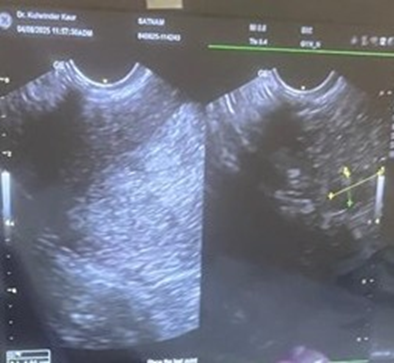

TVS revealed -   Uterus 46.5x39.6mm with  ET-10.6 mm,paradoxically she got   awrong report of endometrial thickness(ET-16.2) reported in some other center   which    actually was the cortical thickness of kidney  -16.2  mm     due to presenceof pelvic kidney which measured 5.9cmx2.2cm.Both ovaries were normal in size.

Figure1-Pelvic Kidney (on right sidewith uteruson left side)